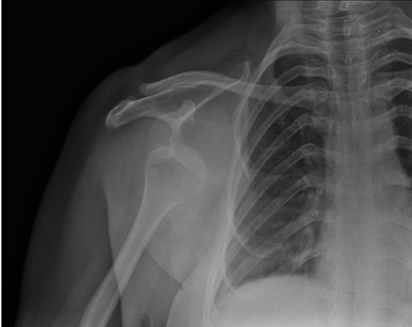

Interscalene Nerve Block for Shoulder Dislocation Gepost op 3 januari 2019 door netwerkvsseh US Probe: Interscalene Nerve Block for Shoulder Dislocation @emDocs.net Dit delen: Delen op X (Opent in een nieuw venster) X Share op Facebook (Opent in een nieuw venster) Facebook Delen op LinkedIn (Opent in een nieuw venster) LinkedIn E-mail een link naar een vriend (Opent in een nieuw venster) E-mail Afdrukken (Opent in een nieuw venster) Print Vind-ik-leuk Aan het laden... Gerelateerd